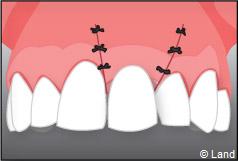

Exemple de 3 dents manquantes remplacées par 3 couronnes sur implants.

Pose des piliers prothétiques et des 3 couronnes scellées.